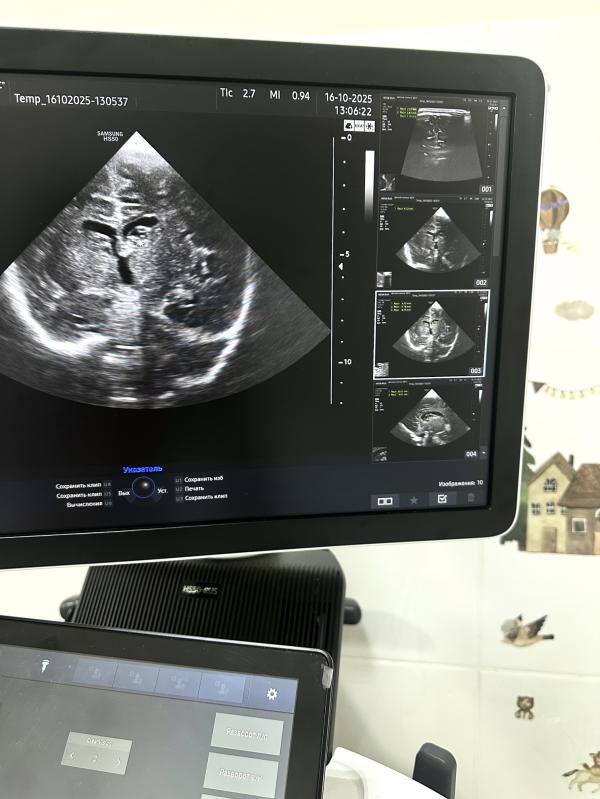

На УЗИ вчера был абсолютно здоровый доношенный малыш, роды естественные, в срок. Единственным моментом стало то, что нейросонография проводилась в возрасте двух месяцев, и мама слегка расстроилась, узнав о наличии кист и небольшом расширении боковых желудочков.

*на узи-снимках указаны кисты и их измерения